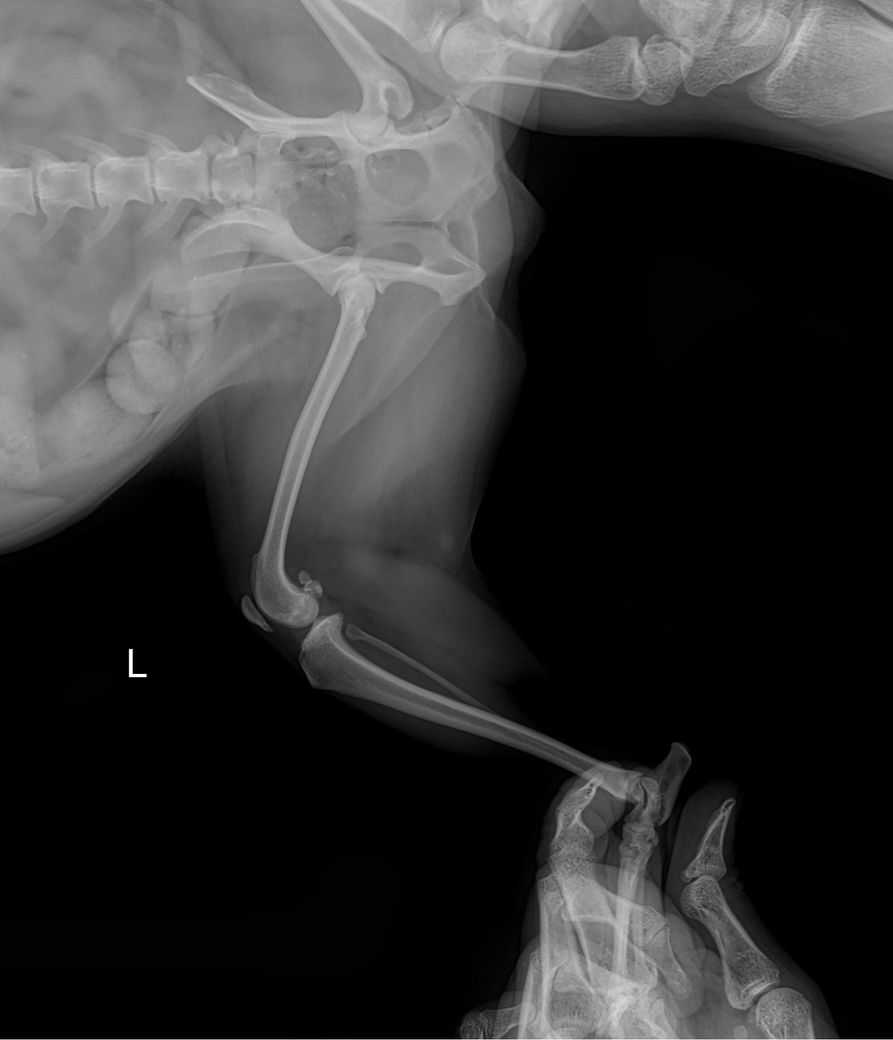

강아지 슬개골 탈구 엑스레이 봐주세요

제 반려견이 다리 한쪽이 아파보여서 병원 데려갔는데 뒷다리가 슬개골 탈구 심하다고 3기에서 4기로 넘어가고 있다고 하더라구요 이제 슬슬 수술 할려고 하는데 철심을 박아야 한다고 하더라구요 선생님들이 봐주셨을 때 정말 심해보이나요?ㅠㅠㅠㅠㅠ 왼쪽 , 오른쪽 중 어디인가요 너무 놀라서 헷갈려요 ㅠㅠ

좌측 슬개골이 내측으로 탈구되어 있는 상태이며.

외측상에서 슬관절 관절낭의 종창이 뚜렷하게 관찰되어 슬개골 탈구와 함께 십자인대의 부분적 손상 가능성이 강력히 의심됩니다. 주치의의 지시대로 빠르게 수술 진행하는게 도움이 됩니다.